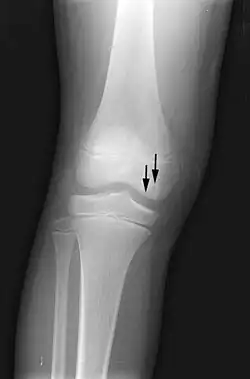

X-ray images of avascular necrosis in the early stages usually appear normal. In later stages it appears relatively more radio-opaque due to the nearby living bone becoming resorbed secondary to reactive hyperemia.[2] The necrotic bone itself does not show increased radiographic opacity, as dead bone cannot undergo bone resorption which is carried out by living osteoclasts.[2] Late radiographic signs also include a radiolucency area following the collapse of subchondral bone (crescent sign) and ringed regions of radiodensity resulting from saponification and calcification of marrow fat following medullary infarcts.

-

Radiography of total avascular necrosis of right humeral head. Woman of 81 years with diabetes of long evolution. -

Radiography of avascular necrosis of left femoral head. Man of 45 years with AIDS. -

Nuclear magnetic resonance of avascular necrosis of left femoral head. Man of 45 years with AIDS. -